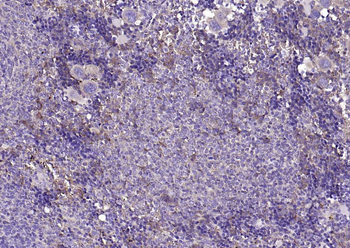

CD56 Antibody

Catalog Number: orb1317086

| Tested applications | IHC, WB |

| Reactivity | Human, Mouse, Rat |

| Dilution range | WB 1:2000, IHC 1:150 |